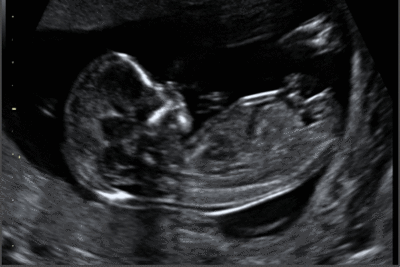

11-13. heti ultrahang szűrés (Genetikai szűrőtesztek)

Az Orosz Medical Center a várandós páciensek számára a terhesség 11-13. hetében, a magzat kromoszóma rendellenességeinek vizsgálatára az alábbi szűrőteszteket kínálja:

1. Kiterjesztett magzati testfelépítés vizsgálat ultrahanggal (FMF, ISUOG és MSZNUT irányelvek szerint)